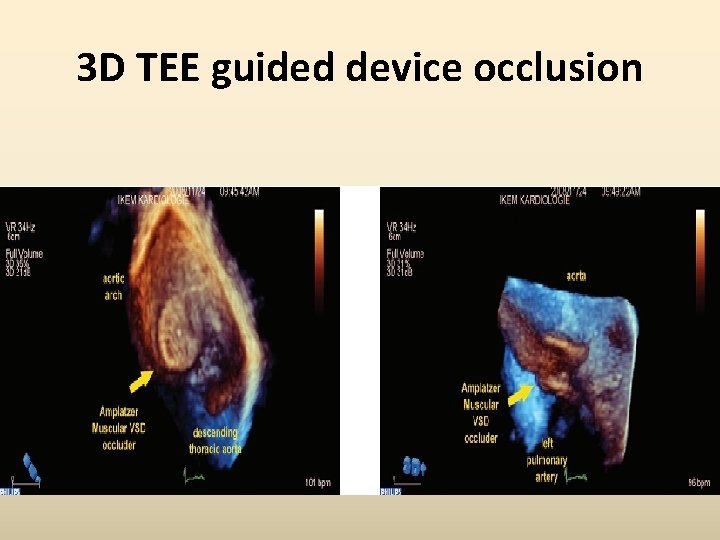

3 D TEE guided device occlusion